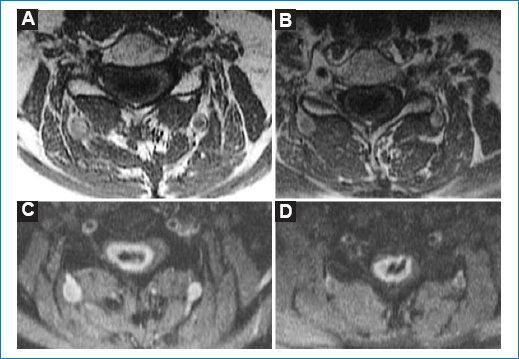

Resonancia magnética

Se aprecia un tumor intradural intramedular que tiene una extensión de cuatro vértebras, desde C3 a C6 (Figs. 14).

Figura 2. Secuencia axial ponderada en T2. Masa heterogénea. (A) Polo superior. (B) Centro donde predomina el componente quístico.

Tiene una posición central con una porción quística intratumoral. La lesión es isointensa en T1 e hiperintensa en T2 y STIR (Figs. 15). Después de administrar contraste paramagnético endovenoso hay realce periférico, especialmente alrededor de la formación quística. Por debajo del polo inferior se ve siringohidromielia de corto trayecto. Las características de las imágenes coinciden con las descripciones que aparecen en la bibliografía35.

Figura 5. (A y B) Secuencia axial en dos niveles ponderada para T1. (B y C) Secuencia axial STIR en dos niveles después de administrar contraste endovenoso. Tras la administración de gadolinio, en secuencia STIR se observa realce periférico en anillo, compatible con heterogeneidad tumoral.